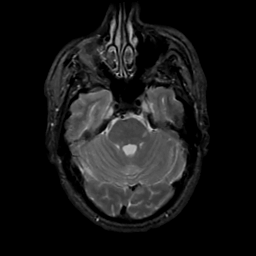

MR Study #3, February 24, 1991 -- Slice #14

[Home][Help][Clinical][Tour 1][Tour 2] Slice 14